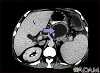

Tests that may help detect pancreatic pseudocyst include:

- Abdominal CT scan